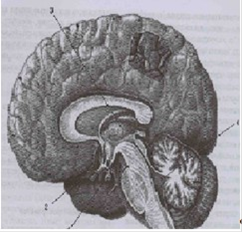

Желудочки головного мозга

В головном мозге различают парный боковой, III и IV желудочки.

Боковой желудочек- полость, залегающая в каждом из полушарий большого мозга. По форме боковой желудочек сравнивают с открытой кпереди и вертикально расположенной подковой.

Боковой желудочек имеет:[1]

центральную часть, ограниченную сверху стволом мозолистого тела, а снизу - дорсальной поверхностью таламуса;

передний рог, расположенный в лобной доле.

нижний рог, расположенный в височной доле;

задний рог, расположенный в затылочной доле

Через сосудистую щель в боковой желудочек заходит сосудистое сплетение, продуцирующее спинномозговую жидкость. Через межжелудочковое отверстие боковой желудочек сообщается с III желудочком

III

желудочек

III желудочек - непарная полость, расположенная вблизи сагиттальной плоскости между двумя таламусами. Спереди через два межжелудочковых отверстия III желудочек сообщается с боковыми желудочками. Сзади III желудочек с помощью водопровода мозга сообщается с IV желудочком. III желудочек содержит сосудистое сплетение III желудочка, вырабатывающее спинномозговую жидкость.

IV

IV желудочек - небольшая полость, заполненная спинномозговой жидкостью.

IV желудочек расположен в пределах ромбовидной ямки и представляет собой узкую щель, заключенную между нею и сзади расположенной сосудистой основой IV желудочка. IV желудочек содержит сосудистое сплетение IV желудочка

[4] желудочки мозга 1.центральный канал,

. IV желудочка, 3.водопровод мозга, 4.IIIжелудочек, 5. межжелудочковое отверстие, 6. центральная,7. передний рог, 8. задний рог,

.нижний рог.